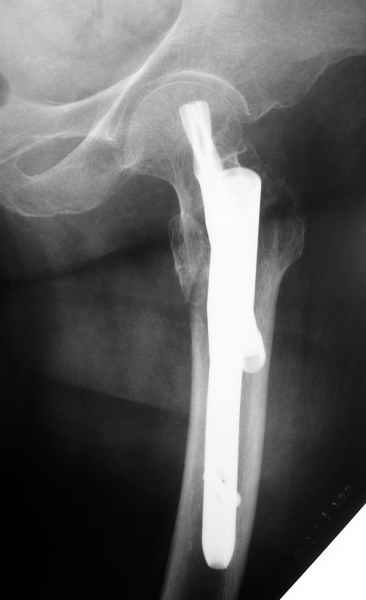

Да, сейчас это и у нас самый напрашивающийся выбор. Сделали гвоздем ChM, картинки в приложении.

У молодых реконструкционный гвоздь самое то. При остеопорозе надо что-то помассивнее.

(Seinsheimer 5 , AO 31 A2.3 or Russell Taylor 2B - see http://www.hwbf.org/ota/bfc/tonyr2/ft028.html

for your sub-intertrochanteric femur fracture case. Excellent work and technique with the reconstruction nailing.